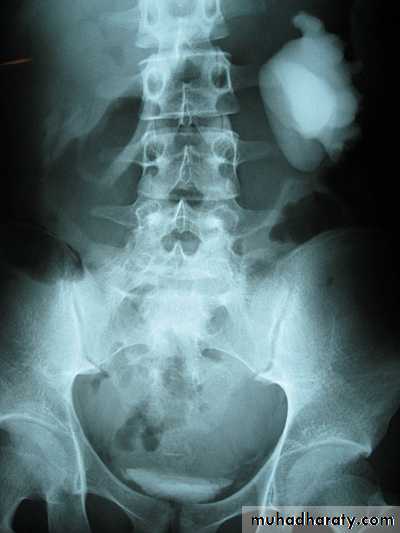

Horse shoe kidney -Kidneys may fail to separate.

-Almost invariably the lower poles remain fused.

-The kidneys axes are more parallel to the spine and malrotated.

-Diagnosis can be made by plain x-ray in some cases.

IVU shows

1. The kidneys at low position .

2.Close to the spine with long axis parallel to the spine .

3. Malrotation manifested by medially directed calyces.

4- The renal pelvis and ureters are anterior and lateral in position .